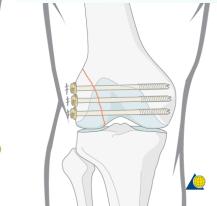

| Screw Types - Cannulated Screws | Feature: Hollow, inserted over a wire for accurate placement in minimally invasive techniques. | , , , , ![]() |